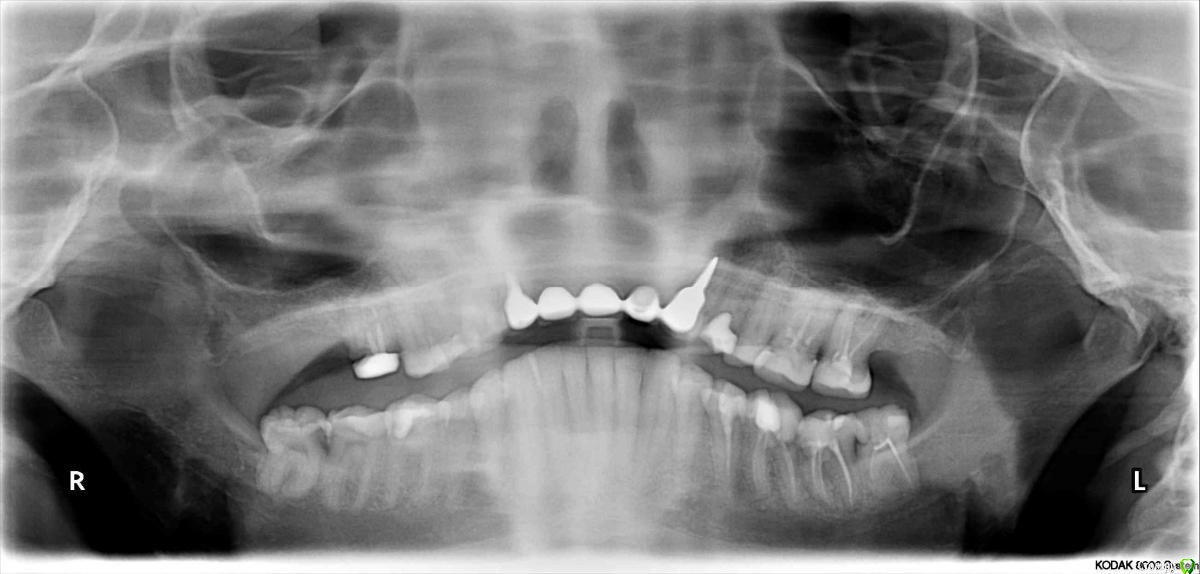

Yashika Опубликовано 22 декабря, 2015 Поделиться Опубликовано 22 декабря, 2015 Добрый вечер.Имею горемычный 6-й справа зуб - давнишнюю жертву советской карательной стоматологии. Депульпирован тысячу лет назад, позже пытались одеть коронку, но пришлось снять и вывести из прикуса - начал давать боли при нажатии. Пытались перелечить, оказалось, что каналы два (по-моему) канала залиты стеклоцементом, пройти не смогли ничем. Сейчас стал сплошным кариесом. Фото прилагаю. После нового года пойду удалять, потом - имплантация. Хирург говорит, удаление грозит сложное. В одной клинике предлагает в процессе удаления применение сгустка PRP, якобы данный метод позволит в будущем избежать необходимость синус-лифтинга над этим зубом и сократит время от удаления до установки импланта. Но цена за удаление зуба в этом случае возрастает до 1/4 стоимости всего имплантирования "под ключ", хотя, разумеется, это значительно меньше, чем проводить синус-лифтинг. Сориентируйте пожалуйста, действительно ли этот путь оптимален и сколь велик шанс, что заплатив за удаление 10 тысяч, мне потом все равно придется делать еще и синус ? Огромное спасибо заранее! 16.bmp Ссылка на комментарий

IvanK Опубликовано 23 декабря, 2015 Поделиться Опубликовано 23 декабря, 2015 Пазуха высоко, возможно и после стандартного удаления ничего не потребуется 2 Ссылка на комментарий